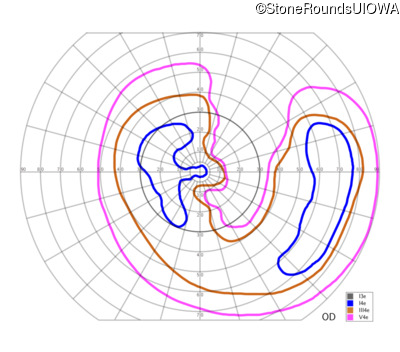

The clinical features supporting the diagnosis of Bardet Biedl syndrome in this patient include: bone-spicule-like pigmentation, narrowed arterioles and macular atrophy on ophthalmoscopy; photoreceptor loss on OCT; ulnar polydactyly, obesity, abnormal cognition, hypertension; and, normally sighted parents.